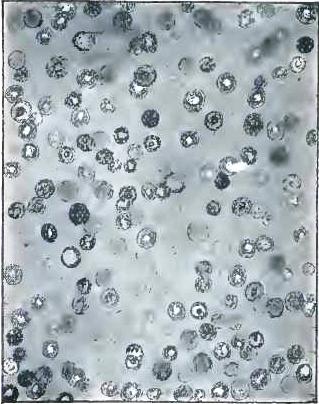

| FIGURE | |

| 1. | MICROCOCCI |

| 2. | BACTERIA |

| 3. | BACILLUS MALARIÆ |

| 4. | BACTERIA FROM GELATIN SOLUTION |

| 5. | VIBRIOS IN GELATIN CULTURE-FLUID |

| 6. | PROTOCOCCUS FROM SLIDES EXPOSED OVER SWAMP-MUD |

| 7. | BACILLI FROM SWAMP-MUD |

| 8. | BACILLI FROM SEPTICÆMIC RABBIT |

| 9. | BACILLI FROM HUMAN SALIVA |

| 10. | BACILLUS ANTHRACIS |

| 11. | BACILLUS TUBERCULOSIS |